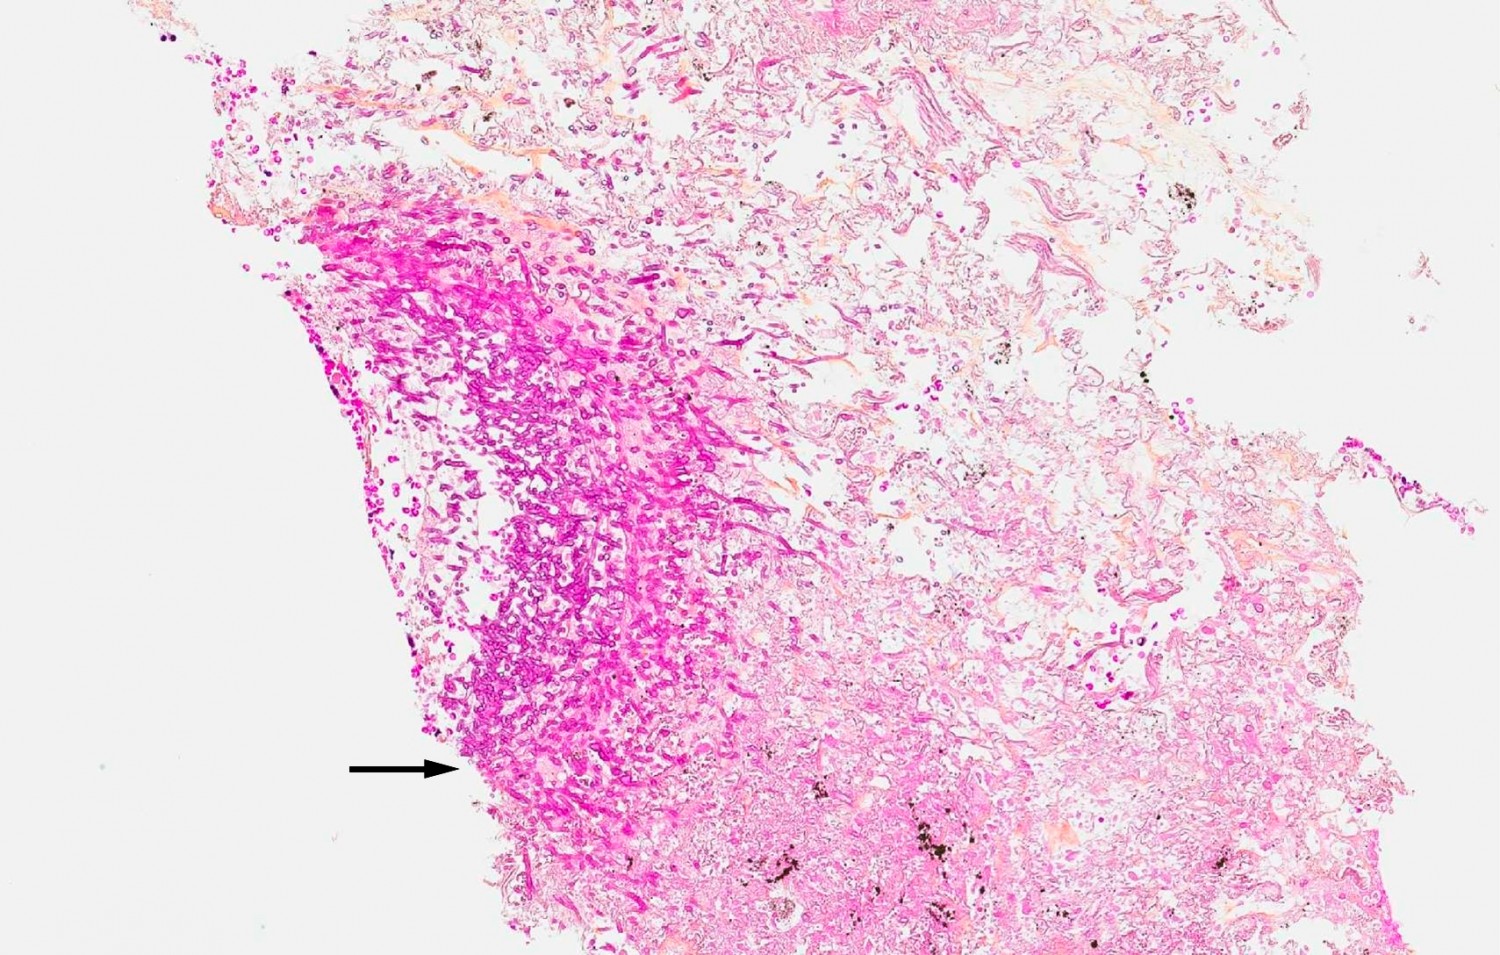

På mistanke om avansert lungekreft kom pasienten inn i et pakkeforløp for videre utredning. Han startet med korttids- og langtidsvirkende opioider (oksykodon) og ble henvist til CT-veiledet lungebiopsi. Inngrepet ble imidlertid utsatt grunnet sterke smerter som gjorde at han ikke klarte å ligge på magen gjennom hele prosedyren. Han hadde fortsatt smerter til tross for tilleggsdoser av opioider og benzodiazepiner, og et nytt inngrep måtte derfor utføres i generell anestesi. Biopsien ble av den grunn forsinket og ble tatt omtrent en måned etter at man først fikk mistanke om malign sykdom. Biopsisvaret viste – overraskende nok – nekrose og hyfer med Aspergillus fumigatus (figur 3). Behandling med vorikonazol ble igangsatt.

Pancoasts syndrom karakteriseres av smerter i skulder eller brystvegg med utstråling til nakke og arm/hånd, som skyldes en oppfylling i den apikale lungedelen (4). Det er sjelden benigne årsaker til syndromet. Disse omfatter som regel benigne fibroserende tumorer og bakterielle infeksjoner, men det er også beskrevet tilfeller av soppinfeksjoner (bl.a. Aspergillus-, Cryptococcus- eller Mucor-arter), både hos immunkompetente og immunkompromitterte pasienter (5, 6). Vår pasient hadde ingen kjent immunsvikt, og videre utredning for sekundær immunsvikt avdekket heller ingen avvik. Man startet antimykotisk behandling med vorikonazol, og etter to uker med denne behandlingen var smertene i regress. Strålebehandlingen måtte utsettes til nærmere avklaring av tumorens etiologi.

Selv om det ikke ble funnet noen atypiske celler i biopsimaterialet og behandling med vorikonazol ble iverksatt, kunne man fremdeles ikke avfeie kreftmistanken. Bildene ble regransket av radiolog, og funnene var fortsatt best forenlig med malignitet, ikke med soppinfeksjon. Dessuten var det flere metastasesuspekte lesjoner i ryggvirvlene (figur 4). Det ble derfor tatt nye biopsier fra en av lesjonene i ryggsøylen. De nye biopsiene, med en rekke immunhistokjemiske analyser, bekreftet at det dreide seg om spredning fra udifferensiert ikke-småcellet lungekreft.

Et biopsisvar er avhengig av den tekniske gjennomføringen av prøvetaking, og man må alltid vurdere hvor representativt prøvesvaret er ut fra en klinisk totalsituasjon. Det første biopsifunnet i vår kasuistikk svekket mistanken om primær lungekreft i favør av invasiv Aspergillus-infeksjon, men kunne ikke forklare metastasesuspekte lesjoner i ryggen. Tilstanden ble tolket som en kombinasjon av lungekreft og invasiv soppinfeksjon som oppsto i svulstens henfallsområde.